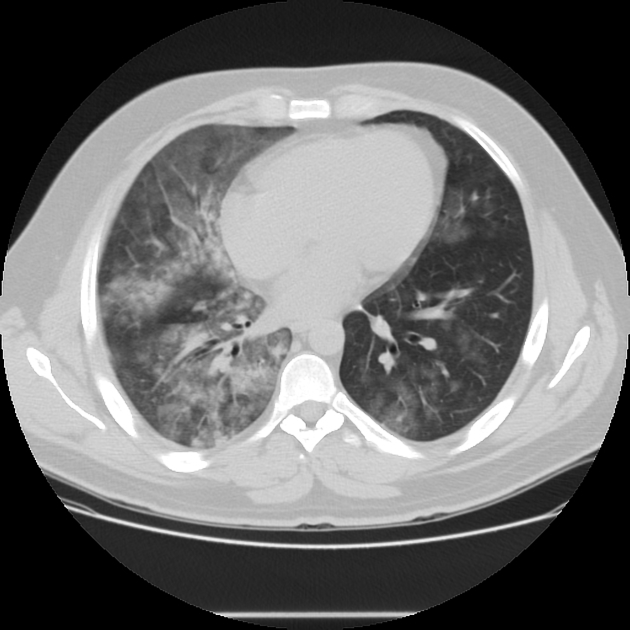

HOMEM, 50 ANOS, INTERNADO POR DISPNEIA + HEMOPTISE DE INÍCIO SÚBITO

áreas de opacidade em vidro fosco associadas a espessamento de septos interlobulares e intralobulares

HEMORRAGIA PULMONAR